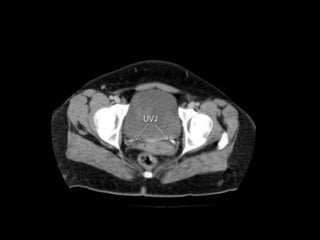

Pelvic peritoneal space Thepelvic peritoneal space is the inferior reflection of the peritoneum over the fundus of the urinary bladder and the front of the rectum at the junction of its middle and lower thirds. In females, the reflection is also over the anterior and posterior surface of the uterus and the upper posterior vagina.In males there is only one potential space for fluid collection posterior to the bladder, the rectovesical pouch. In females there are two potential spaces posterior to the bladder, the uterovesical pouch, and posterior to the uterus the deeper rectouterine pouch (pouch of Douglas). The layers of peritoneum on the anterior and posterior surfaces of the uterus are reflected laterally to the pelvic side walls as the broad ligaments, containing thefallopian tubes.